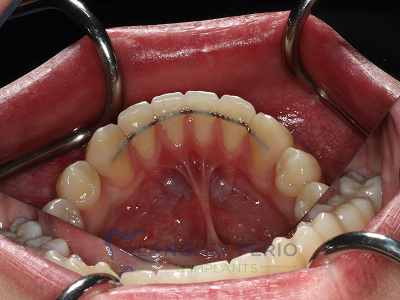

Case 2

Connective tissue grafting was done to cover exposed root surfaces to help to prevent root cavities from developing and reduce temperature sensitivity.